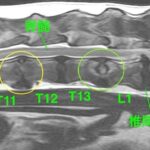

• 【MRI、胸腰部矢状断像、T2強調画像】

画像で見る病気(飼い主様向け)

#19 変性性腰仙椎狭窄症(馬尾症候群)(飼い主様用)

<症例情報> ゴールデンレトリーバー10歳 去勢済みの男の子 主訴:最近腰のあたりを触られ…